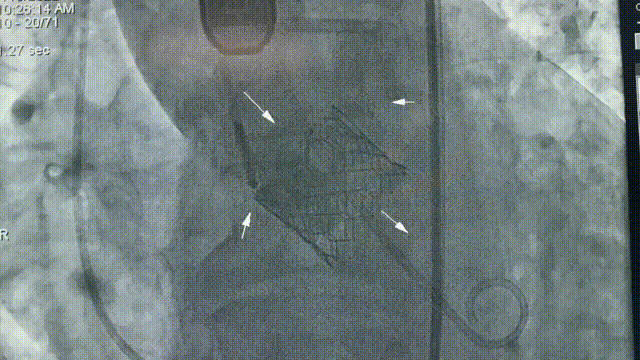

术前CT评估